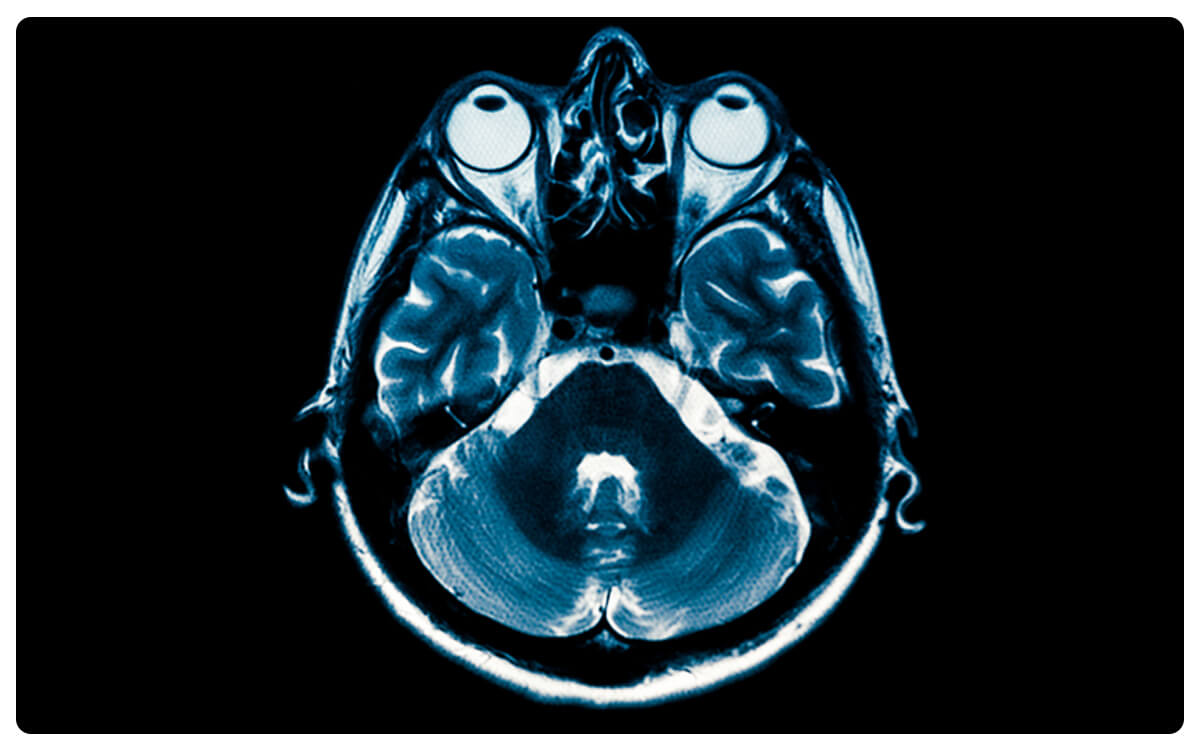

La Tomografía de Oídos Simple y Contrastada, una técnica avanzada de imagen médica, emerge como una herramienta esencial en la exploración minuciosa y detallada de las estructuras auditivas y periauditivas. A través de la tomografía computarizada y la administración de un medio de contraste intravenoso, esta técnica permite la obtención de imágenes tridimensionales de alta resolución que brindan una visión completa de los oídos y posibles afecciones en esta área.

La Tomografía de Oídos Simple y Contrastada desempeña un papel crucial en el diagnóstico y seguimiento de enfermedades auditivas, como infecciones, tumores y malformaciones, proporcionando información valiosa para la detección temprana de trastornos y la toma de decisiones clínicas informadas en el cuidado de la salud auditiva.